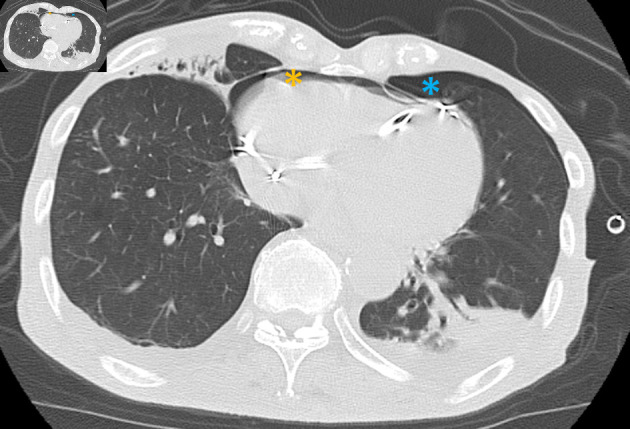

An 83-year-old man underwent dual-chamber pacemaker placement for complete atrioventricular block at another hospital. The active-fixation ventricular lead was positioned on the free wall of the anterior right ventricle. Ventricular pacing failure occurred on the day after pacemaker implantation, and fluoroscopy revealed right ventricular (RV) lead perforation. The patient was transferred to our hospital, and chest computed tomography revealed a severe pneumothorax and moderate pneumopericardium. These symptoms were relieved after chest tube drainage, and the patient's hemodynamics stabilized. The RV lead was percutaneously removed using simple traction under fluoroscopic guidance with cardiac surgical backup and was uneventfully refixed to the RV septum. Although there have been several reports of pneumopericardium caused by atrial lead perforation, there are very few cases related to RV lead. Pneumopericardium complicated by pneumothorax due to RV lead perforation can be relieved using chest tube drainage without the need for pericardiocentesis.